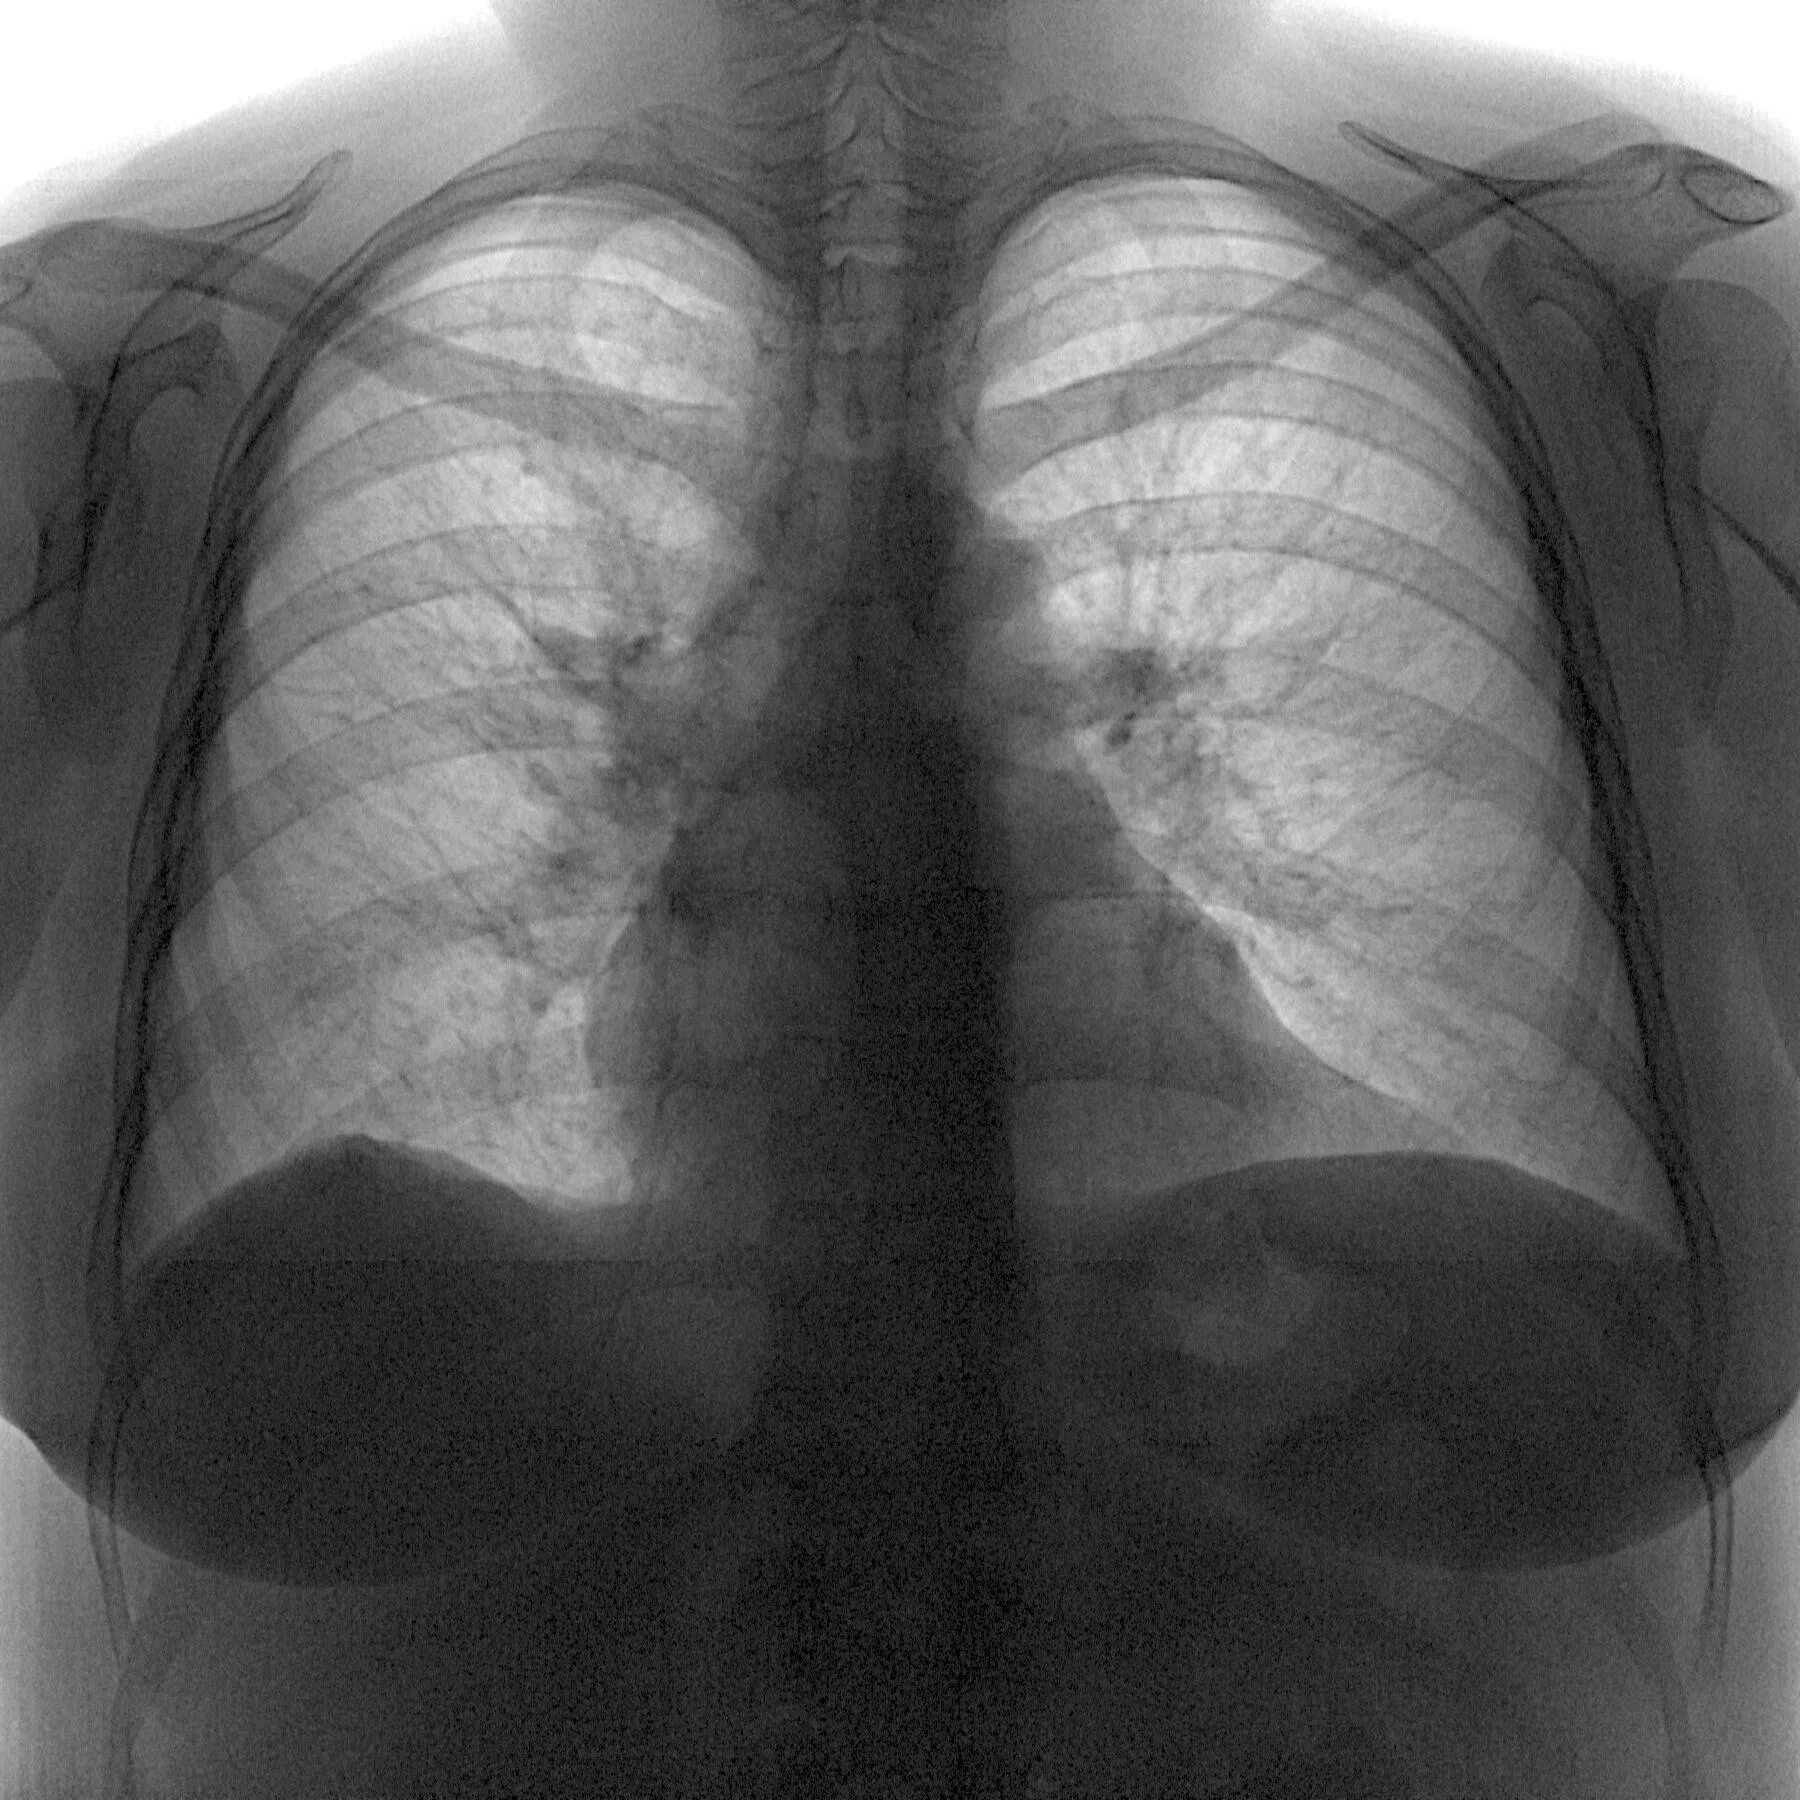

Локальный пневмосклероз легких